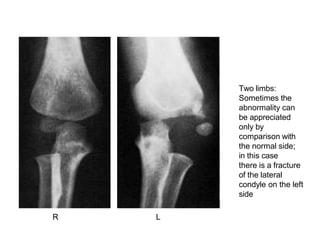

Two limbs – In children, the appearance of

immature epiphyses may confuse the diagnosis

of a fracture; x- rays of the uninjured limb are

needed for comparison.

Two limbs:

Sometimes the

abnormality can

be appreciated

only by

comparison with

the normal side;

in this case

there is a fracture

of the lateral

condyle on the left

side

R L